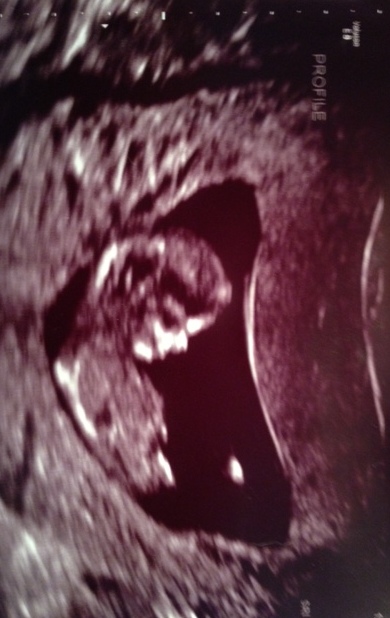

UPDATE: GIRL! NT at 11 wks but measuring 12 wks...does it look like girl?

Okay, so I don't know a lot about nub theory, but from what I read here it is not as accurate at 11 weeks. Does it help that baby was measuring 12 weeks? :)

What do you think? We swayed for girl, and will get results from cell free DNA in a week or two.